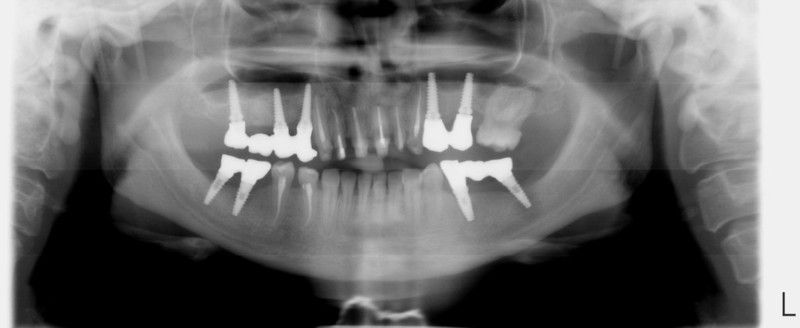

Paciente afectada de Enfermedad Periodontal Avanzada, en ambos maxilares.

En el maxilar superior, perdida ósea vertical generalizada de más de 5 mm, movilidad grado I y grado II.

En maxilar inferior , enfermedad periodontal avanzada del adulto, con perdida de inserción ósea y ligamentosade 5 mm en casi todas las piezas  a excepción de las piezas31 y 41 incisivos  inferiores, con recesisón gingival de atkins y sullivans grado 2.Con defecto vertical superior a 7 mm.

Tratamiento de la enfermedad Periodontal. Con cirugías periodontales de Widman modificado por la técnica de Ramfjiord por cuadrantes, Raspajes curetajes y alisado radicular.

Relleno de los defectos óseos verticales, con material de injerto aloblástico.

Injerto de mentón para conseguir aumento vertical y solucionar la recesión gingival. Fijación del injerto óseo con tornillo de osteosíntesis.